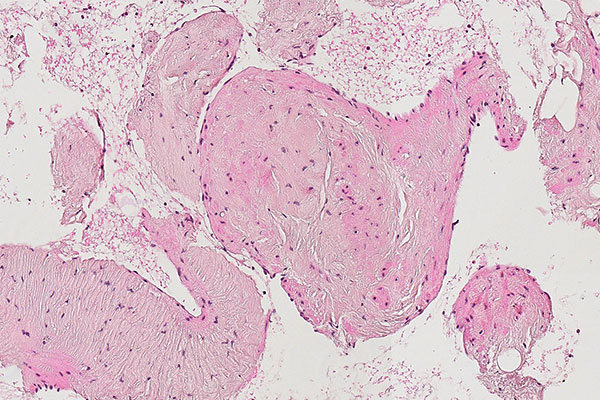

Histopathological section; hematoxylin & eosin (HE) stain, 90x magnification of the punch cylinder. Punch cylinder showing parts of venous malformation with densely packed, irregularly configured large-caliber venous vessel parts. These do not appear tubular as in a normal mature vessel, but as if the vessels are "everted". The lumen looks solid and blood is all around the outside.

Histopathological section; hematoxylin & eosin stain (HE), 160x magnification of the punch cylinder. Here it is clear to see that the irregular, blood-filled spaces of the venous malformation are not solid, but are "voids" partially filled with erythrocytes. The endothelial lining corresponds to the outer border of the visible lesion.

Purely histopathological diagnosis of a lesion as a venous malformation under the microscope is hardly possible without corresponding clinical information and appropriate clinical referral. Nevertheless, there is good evidence that will characterize a venous malformation based on immunohistology and morphology. The venous malformation is a spongy, blood-filled lesion without any real solid parts, similar to a Swiss cheese with a lot of air (air holes = blood-filled cavities; cheese = dysplastic, venous wall structures). Thus, the actual dysplastic vein walls make up only a fraction of the volume in the overall blood-filled lesion and usually appear irregularly branched like a foxhole rather than tubular.